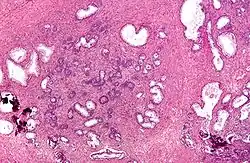

Dans l'HBP, l'architecture de la prostate est globalement préservée avec un aspect nodulaire, mais il existe une hyperplasie des différents constituants.

Les glandes prostatiques sont en nombre augmenté, bordées par une double assise épithéliale. Elles sont souvent le siège de dystrophie (kystisation) ou d'atrophie, et de phénomènes inflammatoires. Les cellules musculaires lisses sont également en nombre augmenté, de même que les fibroblastes de l'interstitium.

L'hyperplasie respective des différents constituants (épithélial, musculaire lisse et fibroblastique) est d'intensité variable suivant les territoires examinés.

![]() |

![]() | |

Histologie d'une prostate normale |

Histologie d'une hypertrophie bénigne de la prostate |